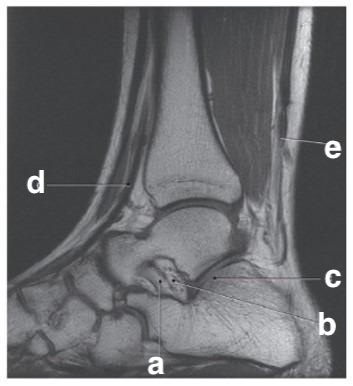

Hook of the hamate

Scaphoid

Radial head

Which letter is the talus?

c

What is letter e?

Achilles tendon